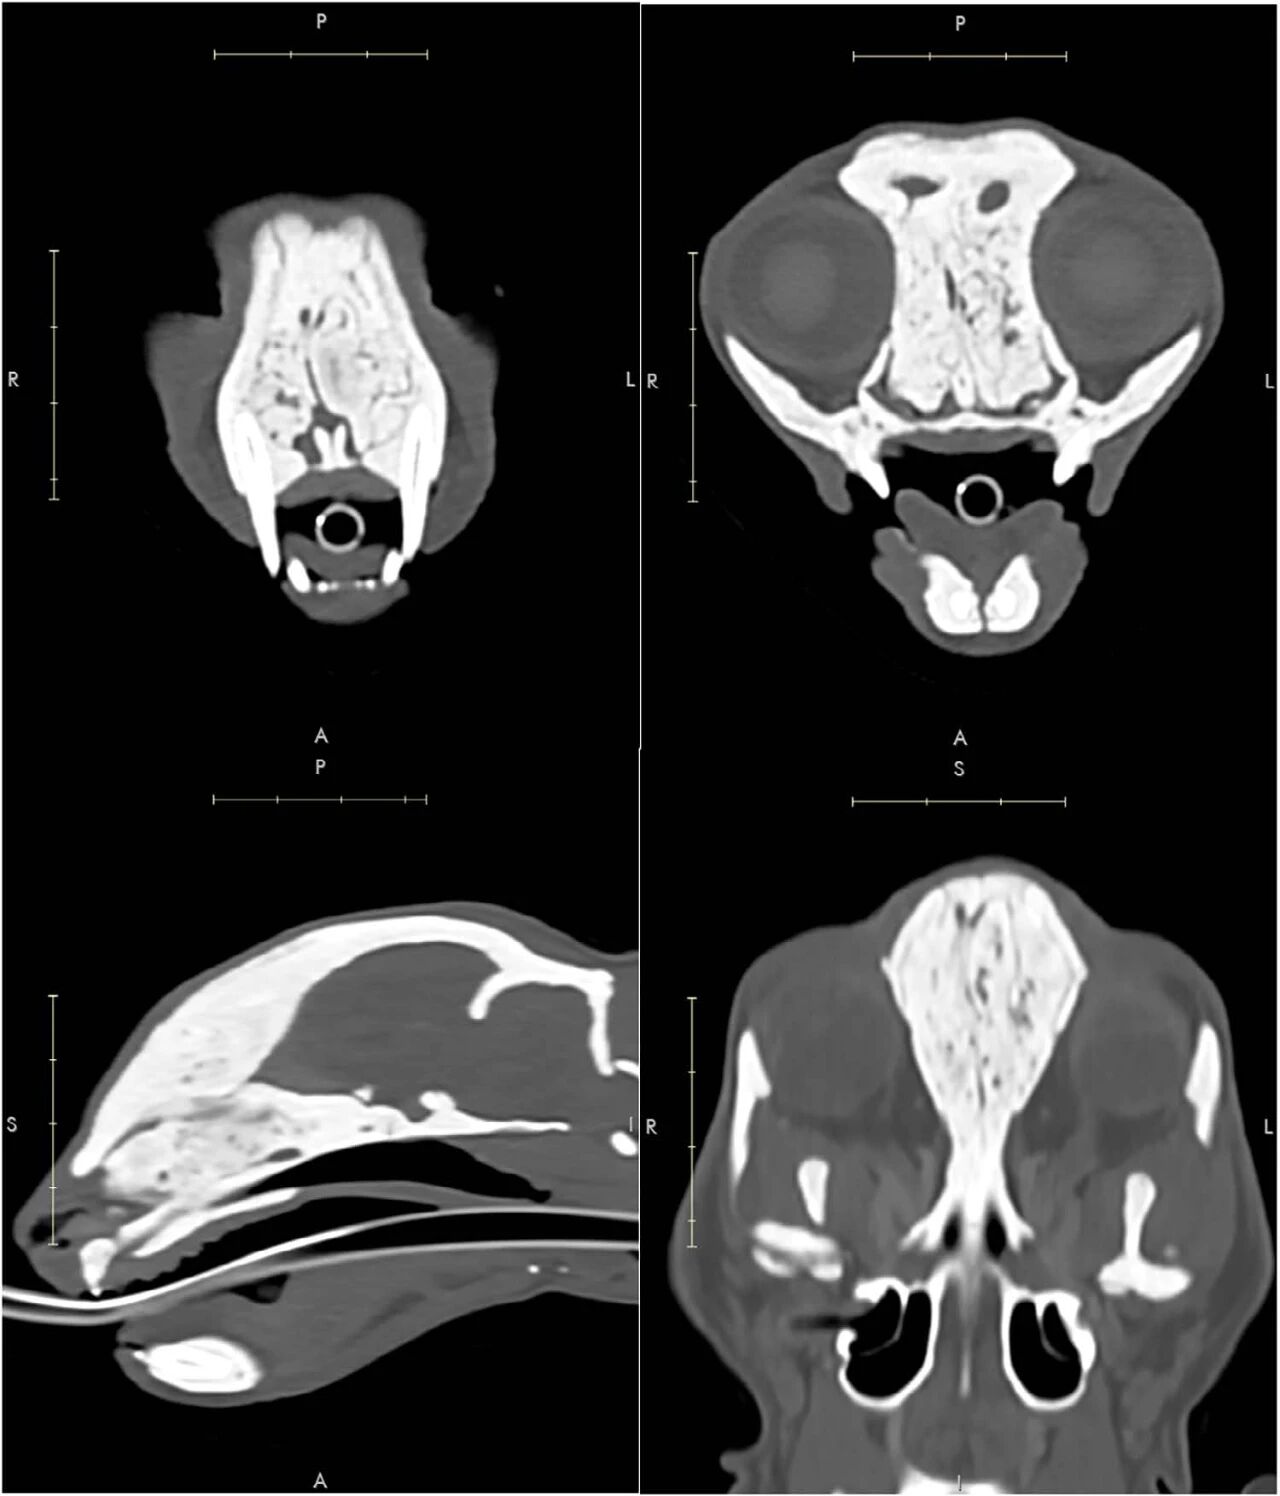

长骨、肋骨、椎骨及骨盆出现弥漫性皮质增厚,骨髓腔密度增高(下图)。多处骨骼皮质增厚,未影响正常骨轮廓及尺寸。脾脏弥漫性肿大,其余腹部器官未见异常。

↑ 胸腹部矢状位CT图像显示,所有骨骼结构均存在广泛弥漫性硬化,包括胸腰椎、骶骨、尾椎、胸骨及骨盆。